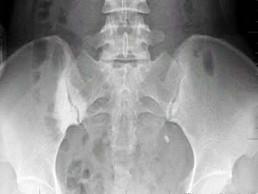

问题 50岁女性患者,因右侧骶髂关节疼痛半年伴左下腹部疼痛,血尿1天入院检查如图所示,最完整的诊断是 ( )

选项 A、右侧致密性骶髂关节炎;左侧输尿管下端结石 B、左侧输尿管上端结石 C、右侧致密性骶髂关节炎 D、左侧输尿管下端结石 E、右侧骶髂关节炎

答案 A